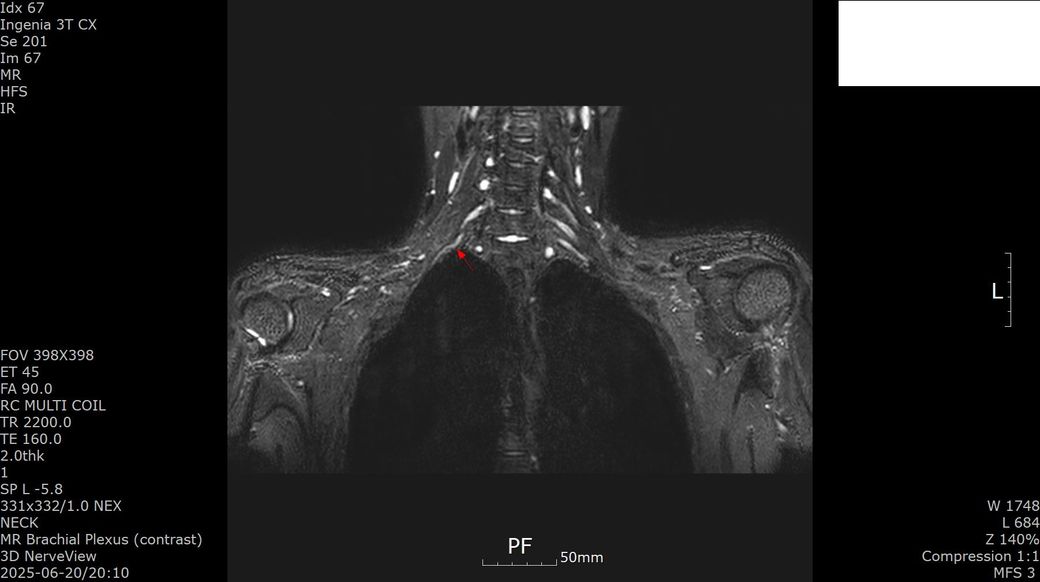

[상완신경총 brachial plexus] mri 판독 부탁드립니다

s/p 2025-01-23

Antereior & middle scalene release, Rt.

1st rib resection, Rt.

Pectoralis minor release, Rt.

Brachial plexus neurolysis, Rt.

2025년 1월경 흉곽출구증후군(우측 사각근 유리술, 우측 제1늑골 제거술, 우측 상완신경총 박리술) 수술한 뒤 5개월 지난 2025년 6월경 상완신경총 mri 검사했습니다.

- 우측팔 supination 안됨

- 이두근 위축 생기고 근력점수 4-에서 3-가 됨

- 엄지, 검지 손가락에 얼얼함 화끈거림 증상이 생김

- 검지 손가락 안 모아짐

- 우측팔뚝 안쪽 부위 감각 무뎌짐

수술 후 몇 가지 합병증이 생겼는데, mri 판독 부탁드립니다. 치료법이 있을까요..?